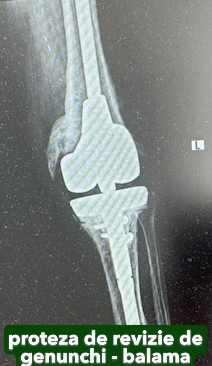

Artroplastia totală de genunchi

Artroplastia totală de genunchi constă în înlocuirea în totalitate a articulației cu o proteză cimentată, care, în prezent, este tot mai performantă.

În funcție de degradarea articulației și de calitatea țesutului osos, pot fi necesare anumite componente suplimentare: augmenturi sau stem tibial.

Dacă genunchiul este instabil, se recomandă protezele stabilizate: LCCK sau balama.

Galerie imagini cu proteze șold și genunchi tratate de dr. Chitea Claudiu Daniel